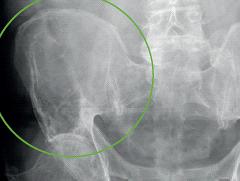

De ziekte van Kahler is een kwaadaardige plasmacelaandoening van het beenmerg die gekenmerkt wordt door een overproductie van afweereiwitten (immunoglobulinen). Klinisch kan deze ziekte zich onder andere presenteren met botpijnen of pathologische fracturen als gevolg van botaantasting. In dit artikel wordt de casus beschreven van een patiënt met een bothaard op een röntgenfoto als gevolg van de ziekte van Kahler. De achtergrond van de ziekte en specifieke bevindingen die gevonden kunnen worden bij het aanvullend onderzoek worden uiteengezet.